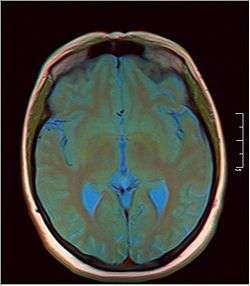

Pineal gland cyst

A pineal gland cyst is a usually benign (non-malignant) cyst in the pineal gland, a small endocrine gland in the brain. Historically, these fluid-filled bodies appeared on 1-4% of magnetic resonance imaging (MRI) brain scans, but were more frequent at death, seen in 21-41% of autopsies.[1] A 2007 study by Pua et al. found a frequency of 23% in brain scans (with a mean diameter of 4.3 mm).[1]